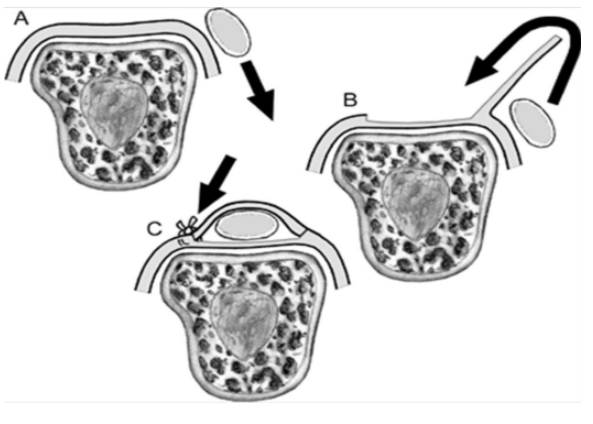

따라서 시상대가 찢어지게 되면 아래 그림처럼 손가락폄근힘줄이 제자리에서 이탈돼서 옆으로 빠지게 됩니다.

아래 모식도에서 보면 잘 이해될 겁니다. 시상대가 찢어지면서 손가락폄근힘줄이 옆으로 훌렁 넘어가버렸습니다.

시상대 손상의 분류는 3가지 타입이 있습니다.

Type I : 폄근 힘줄 불안정성이 없는 시상대 손상

Type II : 폄근 힘줄의 아탈구가 동반된 손상

Type III : 폄근 힘줄이 탈구가 동반된 손상